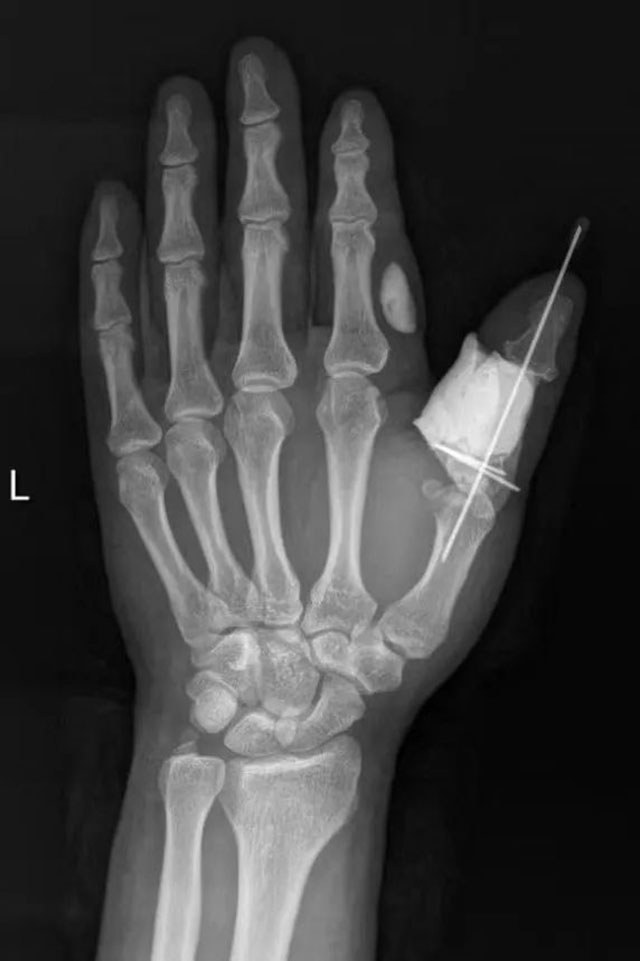

陈孝均与患者及家属充分沟通后,立即为赵大哥实施了第一次手术:创口清创,残缺骨骼临时固定,骨缺损区用抗生素骨水泥临时旷置。

据陈孝均介绍,骨水泥就是骨粘固剂,是一种用于骨科手术的医用材料,由于它的部分物理性质以及凝固后外观和性状颇像建筑、装修用的白水泥而得名,可以起到支撑断裂的骨头和保护创面的作用。